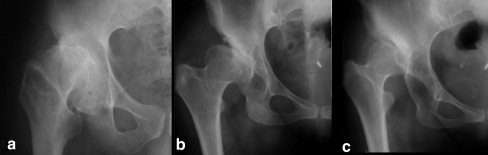

For the classification of congenital hip disease (CHD) in adults various systems have been proposed [1, 12, 16, 17]. The Hartofilakidis et al. classification system, initially published in 1988, relies on intraoperative findings to describe the hip pathology encountered during the operation [1, 2]. The major distinguishing feature is the description of acetabular deformity (Table 1). This classification system encompasses three types of deformity in the adult hip, i.e. dysplasia, low dislocation and high dislocation (Fig. 1). The demographics and clinical presentation vary between the various CHD types [13]. Patients with dysplasia become symptomatic later in adult life, the anatomical distortion of the femur and the acetabulum is milder, the operation is simpler and the results of total hip replacement (THR) are generally better compared to the more severe forms of the disease [14]. In 20–50% of adults with hip osteoarthritis the underlying problem is hip dysplasia [9].

Fig. 1.

The radiological appearance of the three types of CHD in adults: dysplasia (a), low dislocation (b) and high dislocation (c)